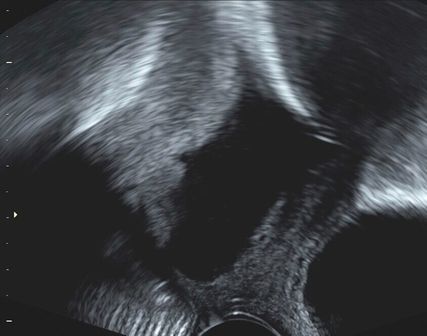

Abb. 1: Transvaginaler Ultraschall: liegende Cerclage (roter Pfeil) mit TMMV

Aufgrund der Vorgeschichte wurde mit der Patientin die Durchführung einer prophylaktischen Cerclage besprochen, welche von der Patientin gewünscht wurde. In der Voruntersuchung zeigten sich im Ultraschall eine tiefsitzende Hinterwandplazenta sowie Escherichia coli im Vaginalabstrich. Man entschied sich aufgrund der tiefsitzenden Plazenta für initial regelmässige sonografische Verlaufskontrollen zur zeitgerechten Indikation der Cerclagedurchführung. Zudem erfolgte eine Behandlung des Vaginalinfektes mit Ceftriaxon (intravenös) aufgrund der Vorgeschichte. Im weiteren Verlauf erfolgte die problemlose Durchführung der primären Cerclage (Abb.1) inklusive TMMV bei 17+2 SSW, nachdem sich die Plazenta nun 28mm vom inneren Muttermund entfernt zeigte bei einer Zervixlänge von 39mm.